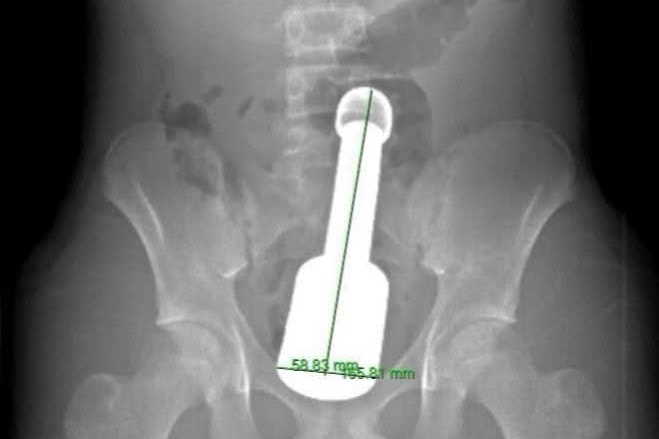

Cụ thể, bệnh nhân N.K.N (15 tuổi, Hà Đông, Hà Nội) nhập viện trong đêm với biểu hiện đau dữ dội vùng hạ vị. Kết quả chẩn đoán hình ảnh cho thấy một dị vật kim loại kích thước lớn mắc kẹt sâu trong trực tràng, gây chèn ép các cơ quan vùng chậu và tiềm ẩn nhiều nguy cơ biến chứng nếu xử trí không thận trọng.

Dị vật là một chiếc chày dài 18cm, đường kính 6cm, gần đạt giới hạn tối đa của cơ thắt hậu môn ở lứa tuổi thiếu niên. Ngoài kích thước lớn và trọng lượng nặng, dị vật còn tạo ra “hiệu ứng chân không” phía trên đỉnh, khiến nó bị hút chặt vào lòng trực tràng.

Hình ảnh phim chụp X. quang cho bệnh nhân. Ảnh: BVCC